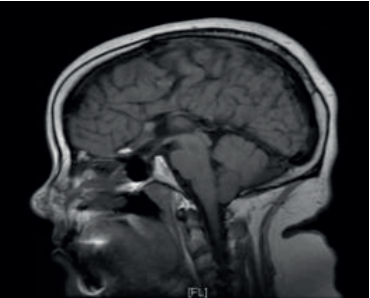

Paciente de sexo femenino, 37 años, derivada desde la policlínica de fertilidad. A los 11 años, en el contexto de evaluación por talla baja (debajo de 2 desvíos estándar (DE) de la media para edad y sexo), con hipocrecimiento (velocidad de crecimiento menor a -1 DE por más de un año, acompañado de talla baja) y retraso del desarrollo puberal, se diagnosticó hipogonadismo hipogonadotrófico y déficit de GH. Como etiología, presenta síndrome de De Morsier diagnosticado por resonancia nuclear magnética (RNM) a la misma edad que evidenció ausencia de septum pellucidum, hipoplasia del nervio óptico con hipoplasia de cuerpo calloso, tallo hipofisario y quiasma óptico traccionados ocupando la silla turca. Además, no se reconoce la neurohipófisis (figuras 1,2 y3).

La clínica es muy variada. Pueden ocurrir alteraciones visuales, neurológicas y endócrinas. Las alteraciones visuales ocurren secundariamente a la hipoplasia del nervio óptico, que van desde un daño parcial en la visión hasta ceguera, también se asocia a estrabismo y nistagmo. Esta paciente presentó desprendimiento de retina congénito en ojo derecho y nistagmo ocular bilateral. Las secuelas neurológicas comprenden retraso en el desarrollo cognitivo, convulsiones, hasta incluso parálisis cerebral. Cuando se tiene al menos una sospecha de SOD, que en esta paciente se evidenció por el fenotipo al nacimiento, labio leporino, trastorno ocular y nistagmo, se debe solicitar una RNM para evaluar anormalidades del hipotálamo-hipófisis y posibles defectos de la línea media5. Para el diagnóstico, deben estar presentes dos de tres criterios: ausencia del septum pellucidum, disgenesia del cuerpo calloso e hipoplasia del nervio óptico. Otros hallazgos posibles son microftalmia o anoftalmia, coloboma, hipófisis ectópica o hipoplasia, tallo hipofisario hipoplásico7. Los ejes hipofisarios más frecuentemente afectados son el somatotropo, corticotropo, tirotropo y déficit de hormona antidiurética (ADH). Esta paciente se presentó con un déficit de GH y un hipogonadismo hipogonadotrófico. En un estudio realizado en Estados Unidos, en 1984, observaron que de una muestra de 16 pacientes con SOD en un seguimiento de 3,5 años. El orden y grado de afectación de los ejes hormonales era similar a lo reportado en la literatura hasta el momento. Encontraron que 73% presentaba déficit GH aislada, y 34% de deficiencia de ACTH. Le siguen el déficit de hormona tirotropa (TSH) y ADH en 24% y 21%, respectivamente8. Se concluye que los déficits hormonales son frecuentes y pueden progresar en el tiempo, por lo que la evaluación endocrinológica regular es necesaria para la correcta sustitución y prevención de comorbilidades asociadas al hipopituitarismo.